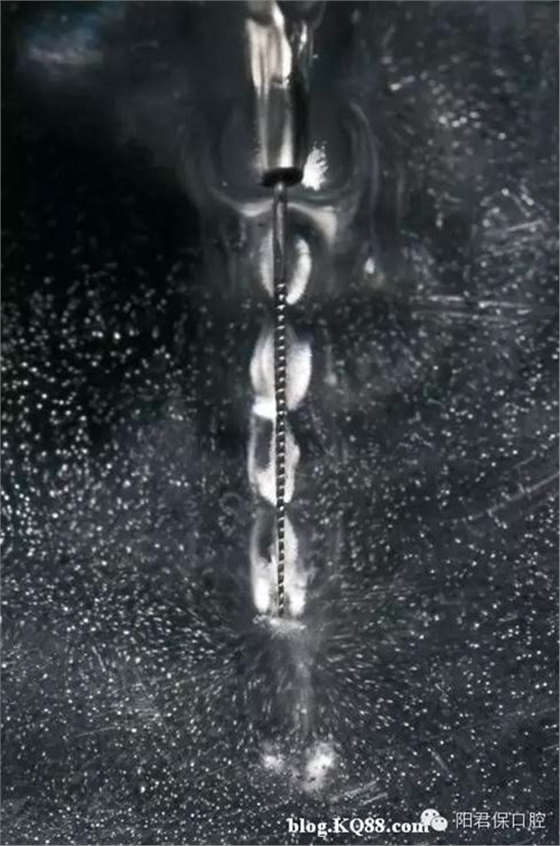

超聲蕩洗能增強清洗效果,超聲銼的持續(xù)震動可以將次氯酸鈉傳送到根尖部,也可以加熱根管內(nèi)的次氯酸鈉,超聲震動的頻率是25-40kHz,超聲在根管內(nèi)形成超聲流,同時在銼尖端形成渦流。超聲流有殺滅細菌和破壞酶的作用,超聲不能用于根管成形,只能用于根管蕩洗,所以根管塑形完成后再用超聲,否則可能會形成臺階或穿孔。

十三,超聲蕩洗的方法 超聲銼非工作狀態(tài)提前插入根管試合適,量好長度,然后震動后再進入根管做上下1mm的運動,盡量深入根管距離狹窄部2-3mm,但超聲銼絕不能碰觸到根管的任何部位。